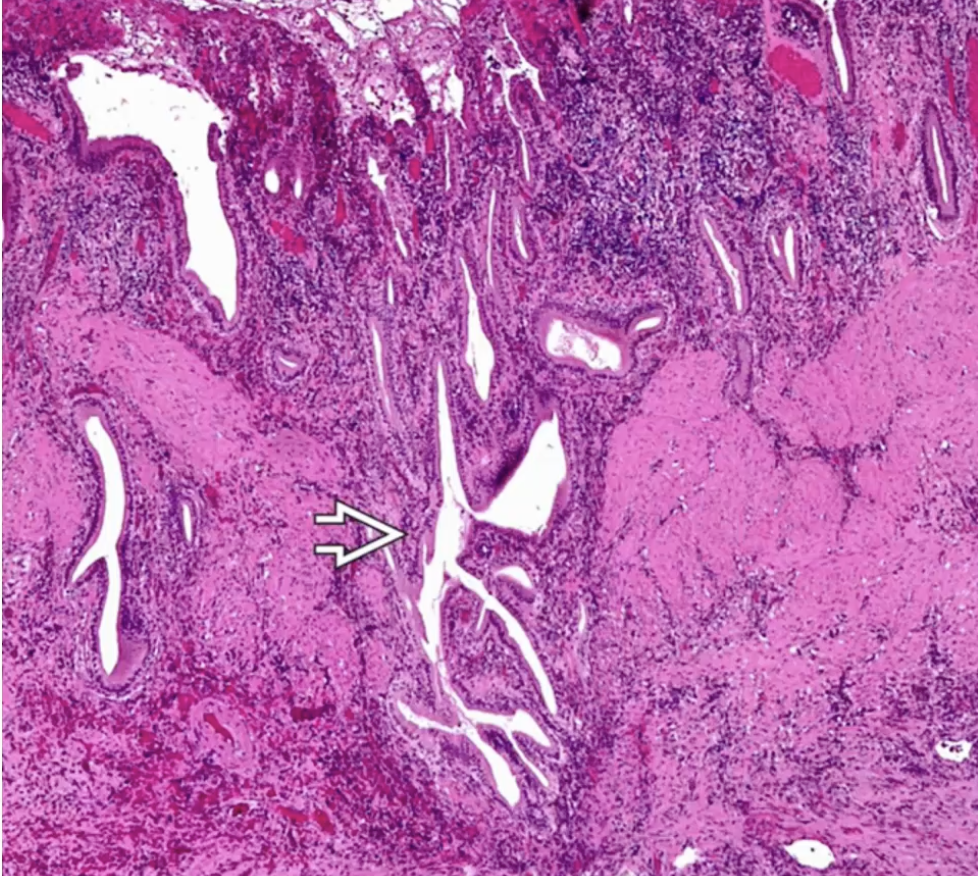

Xanthogranulomatous Cholecystitis

Follicular Cholecystitis